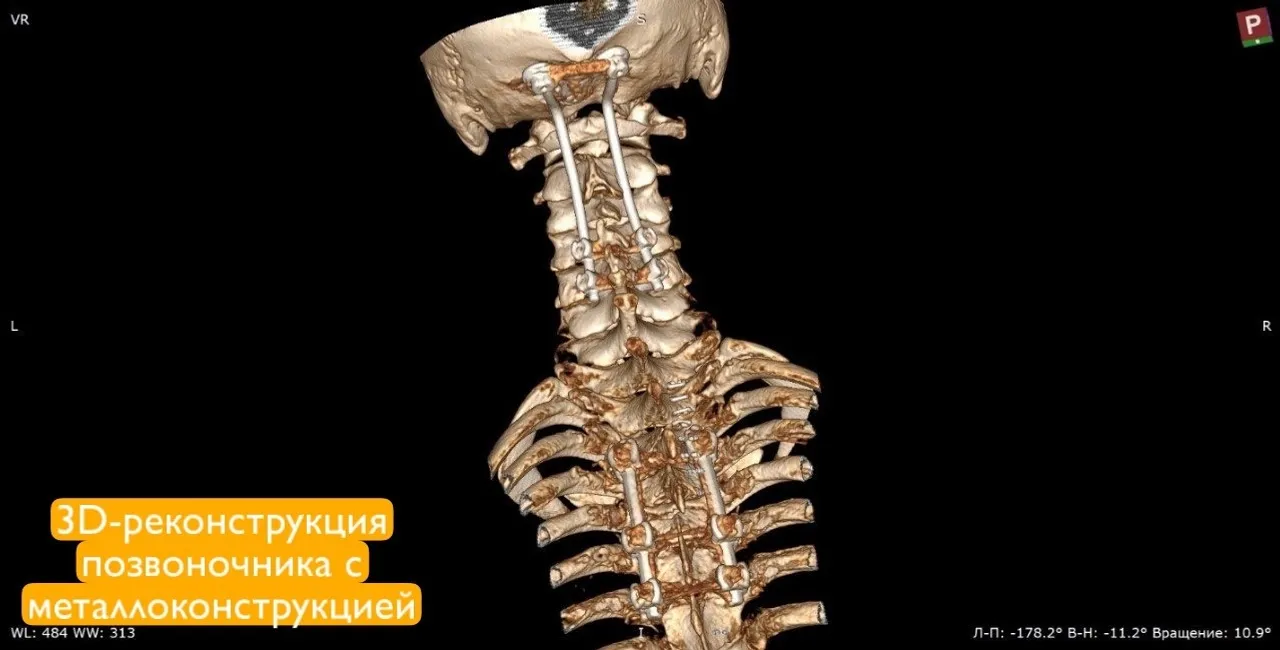

Чтобы помочь молодому человеку вернуться к полноценной жизни, врачи провели операцию для фиксации шейного отдела специальной конструкцией. Операция длилась 2,5 часа. В тот же день пациент смог встать на ноги, а спустя неделю его выписали домой в удовлетворительном состоянии, сообщил главврач Алик Янышев.